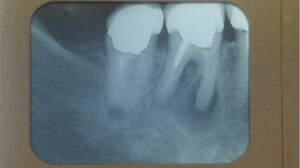

過去に根管治療をなされた患者様ですが、歯の根っこの先まで薬が詰まっておらず、細菌感染を起こして根っこの先に炎症(黒い部分)が出来ています。

古い詰め物、感染した根管内の歯質を除去しています。